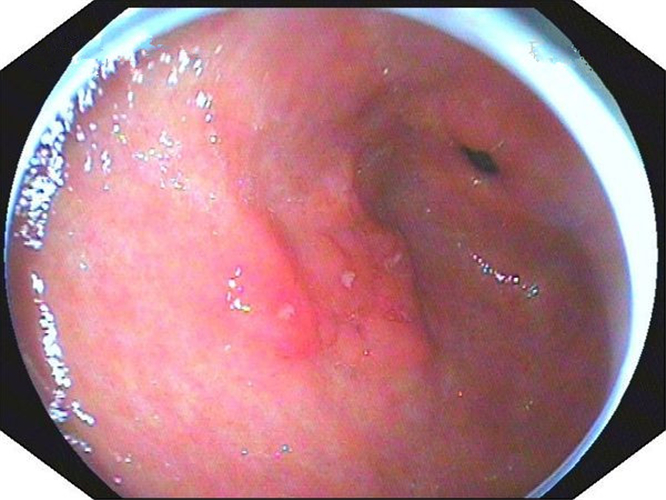

中型淺表萎縮慢性胃炎